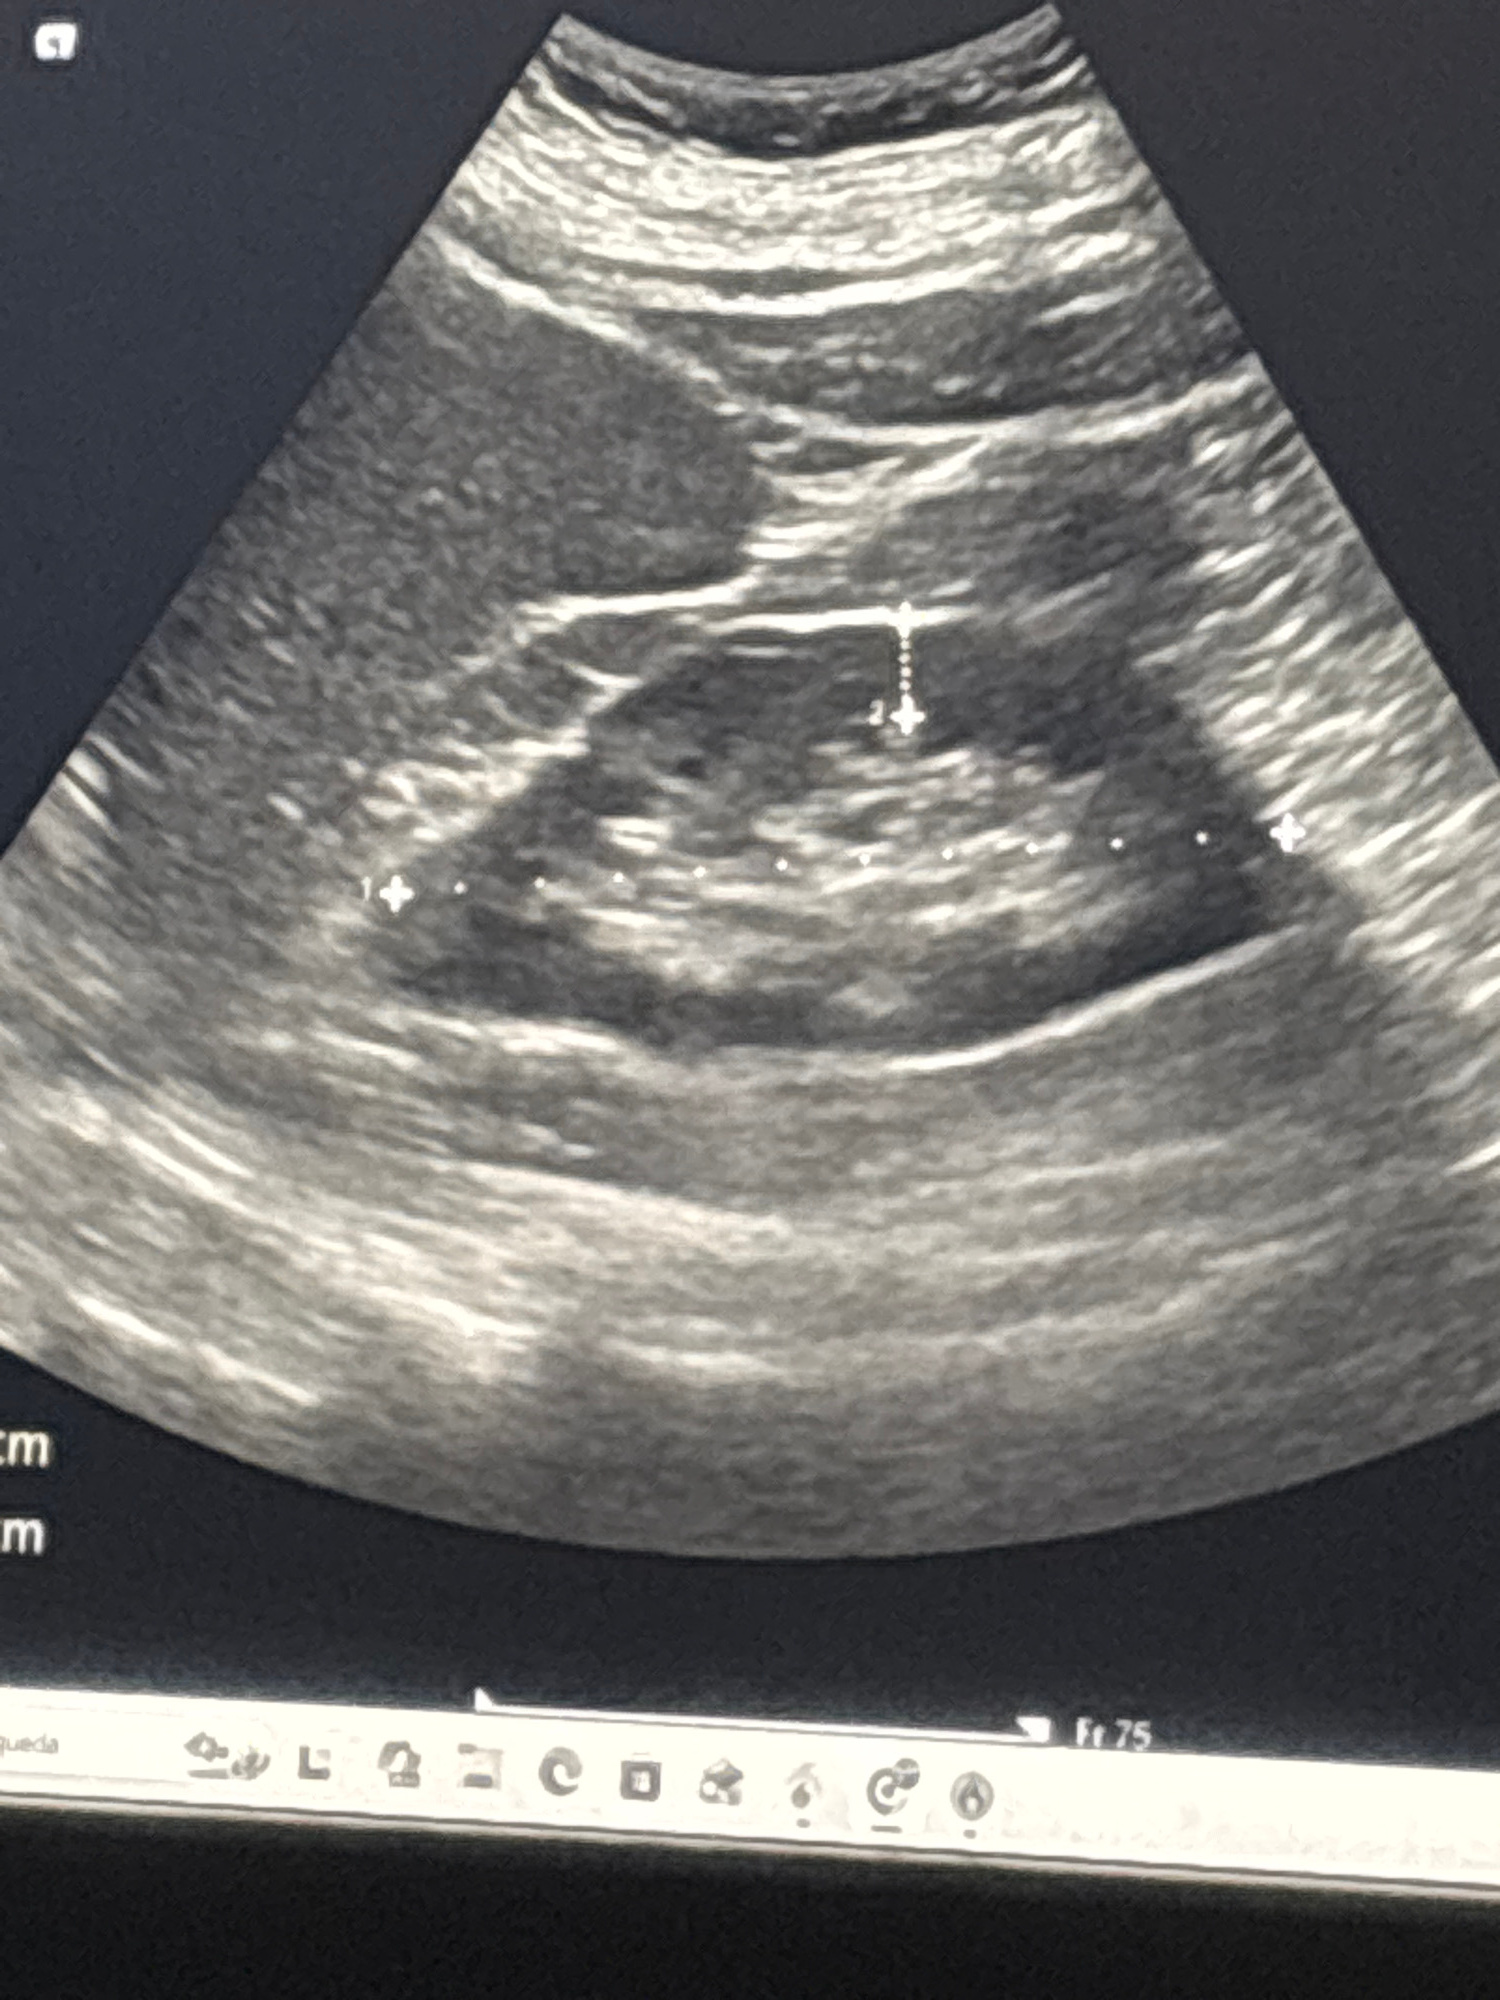

The image is a grayscale ultrasound scan. The scan shows a roughly circular structure with mixed echogenicity, suggesting a fluid-filled or complex mass. Measurement markers are visible, indicating di…read more